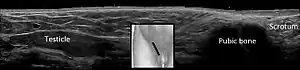

Cryptorchidism on scrotal ultrasound

Scrotal ultrasonography of undescended testis: (a) Normal testis in the scrotum (b) Atrophic and decreased echogenicity of the contralateral testis of the same person seen in the inguinal region

In the minority of cases with bilaterally nonpalpable testes, further testing to locate the testes, assess their function, and exclude additional problems is often useful. Scrotal ultrasound or magnetic resonance imaging performed and interpreted by a radiologist can often locate the testes while confirming absence of a uterus. At ultrasound, the undescended testis usually appears small, less echogenic than the contralateral normal testis and usually located in the inguinal region. With color Doppler ultrasonography, the vascularity of the undescended testis is poor.